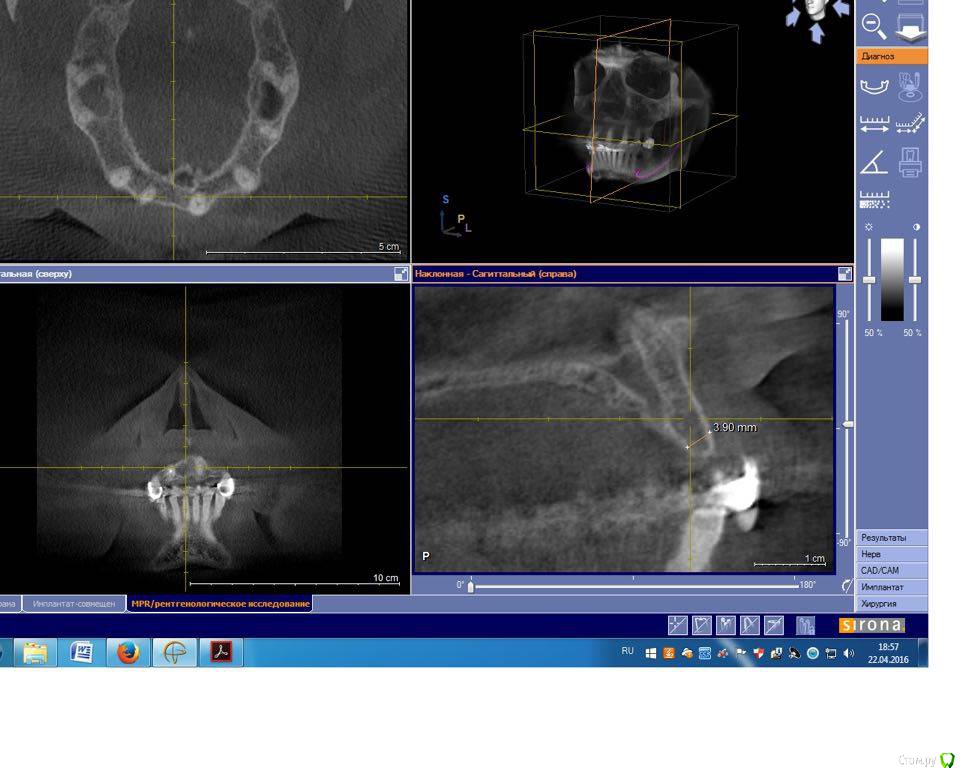

togrul Опубликовано 4 мая, 2016 Поделиться Опубликовано 4 мая, 2016 Добрый день необходим совет по планированию. Планируем удалить зуб 1.2 + одномоментно имплантат Импро 3.6 + ССТ. в области 11 зуба имплантат 3.6 + ССт. у пациента сахарный диабет в районе 8.И 2 вариант НТР в области 11 + имплантация отсрочено. хочу услышать мнение более опытных коллег. буду благодарен. Ссылка на комментарий

togrul Опубликовано 6 мая, 2016 Автор Поделиться Опубликовано 6 мая, 2016 Панорамный снимок Ссылка на комментарий